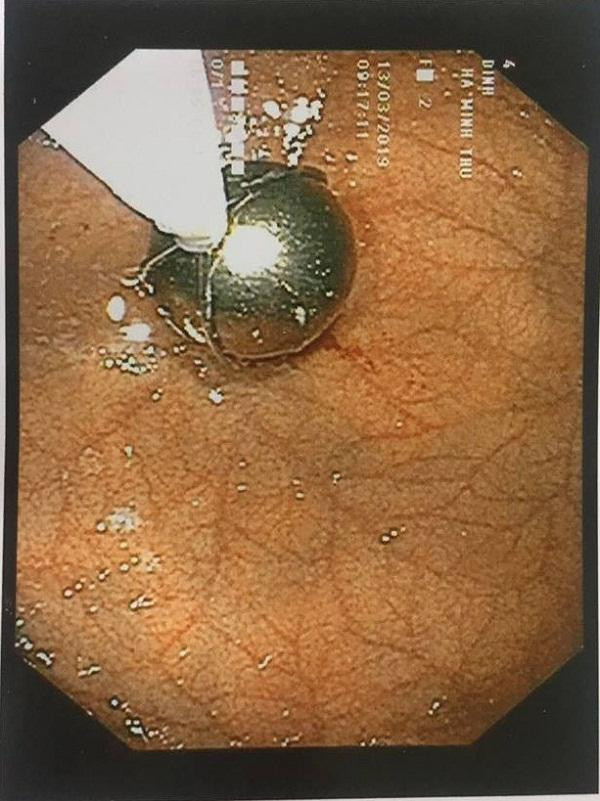

Viên bi sắt được gắp ra ngoài

Bác sĩ đã phải dùng rọ gắp sỏi chuyên biệt và tập trung tinh thần cao độ để gắp viên bi sắt ra ngoài

Bác sĩ Hội cũng cho biết thêm, nội soi gắp dị vật cho trẻ nhỏ nói chung và ở trường hợp bé T. rất phức tạp, các sự cố y khoa xảy ra khi nội soi tai mũi họng đa phần là do tâm lý trẻ lo sợ, không hợp tác, cựa quậy khi nội soi.

Hình dạng dị vật tròn và rất trơn tuột, gắp ra rất khó khăn, bác sĩ đã phải dùng rọ gắp sỏi chuyên biệt và tập trung tinh thần cao độ, thận trọng hết sức. Nếu sơ sấy để viên bi rơi vào khí quản thì chỉ sau 3 phút trẻ có thể bị di chứng não suốt đời và trong vòng 5 phút trẻ có nguy cơ bị tử vong.